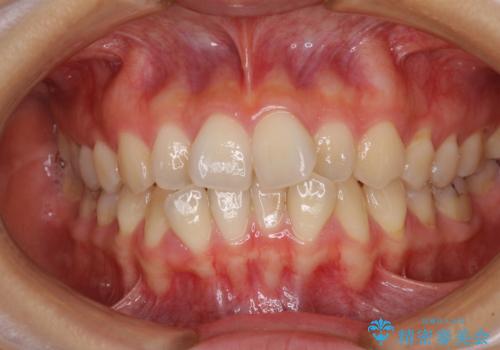

ディープバイトをインビザライン矯正で改善